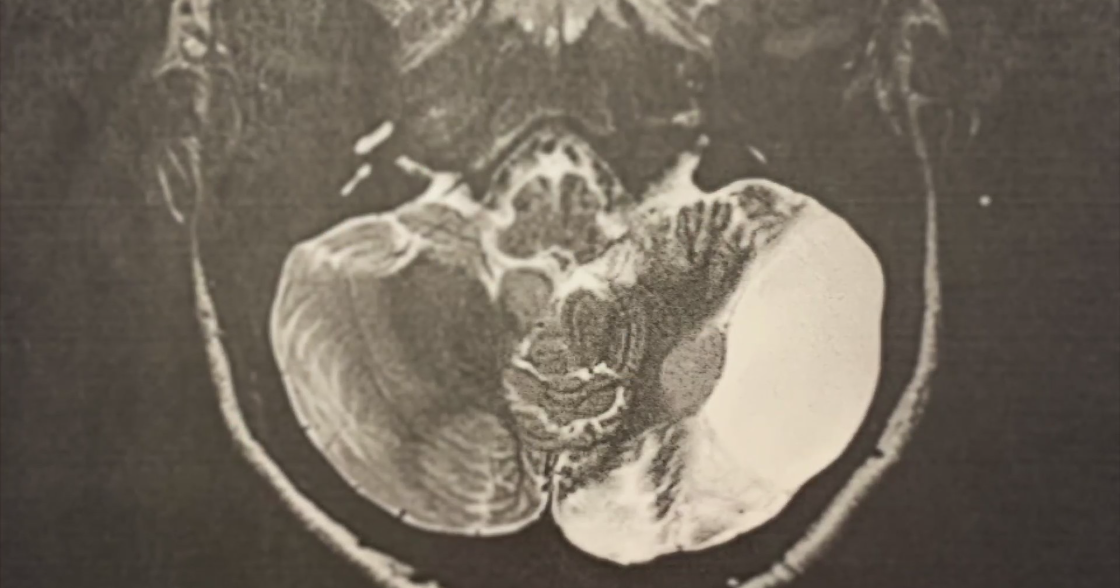

At 19 months old, doctors diagnosed Trucker Dukes, now 3, with Stage 4 neuroblastoma, a cancer in the adrenal glands that caused him and his mother to move temporarily from Maui to New York City for treatment.

Trucker has a fellow friend on duty – River Laurence, 4. He too is receiving treatment at Memorial Sloan Kettering Cancer Center for Stage 4 neuroblastoma.

Doctors said River has a tumor that likely will not go away. Trucker still has a fight ahead of him.